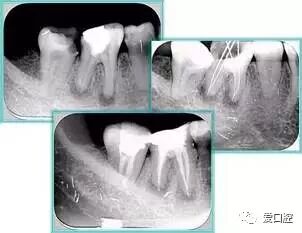

根管初步预备完毕后用 H 锉提拉,之后进行工作长度再确认。插上牙胶尖,拍摄 X 线片,观察主牙胶尖位置。

6. 术后 X 线片

术后 X 线片用来评定根管充填 长度、致密度(管壁清晰、侧枝)等指标。

左图为根管充填术后 X 线片。图中可见,根管充填较好。右下图有白色小点,为侧方加压导致糊剂挤出所致,表明根管充填比较致密。

致密、恰到好处的充填可去除干净根管里感染灶,机体逐渐恢复。

多根牙时候需进行偏移投照,正位投照无法说明具体哪根牙根管充填效果。